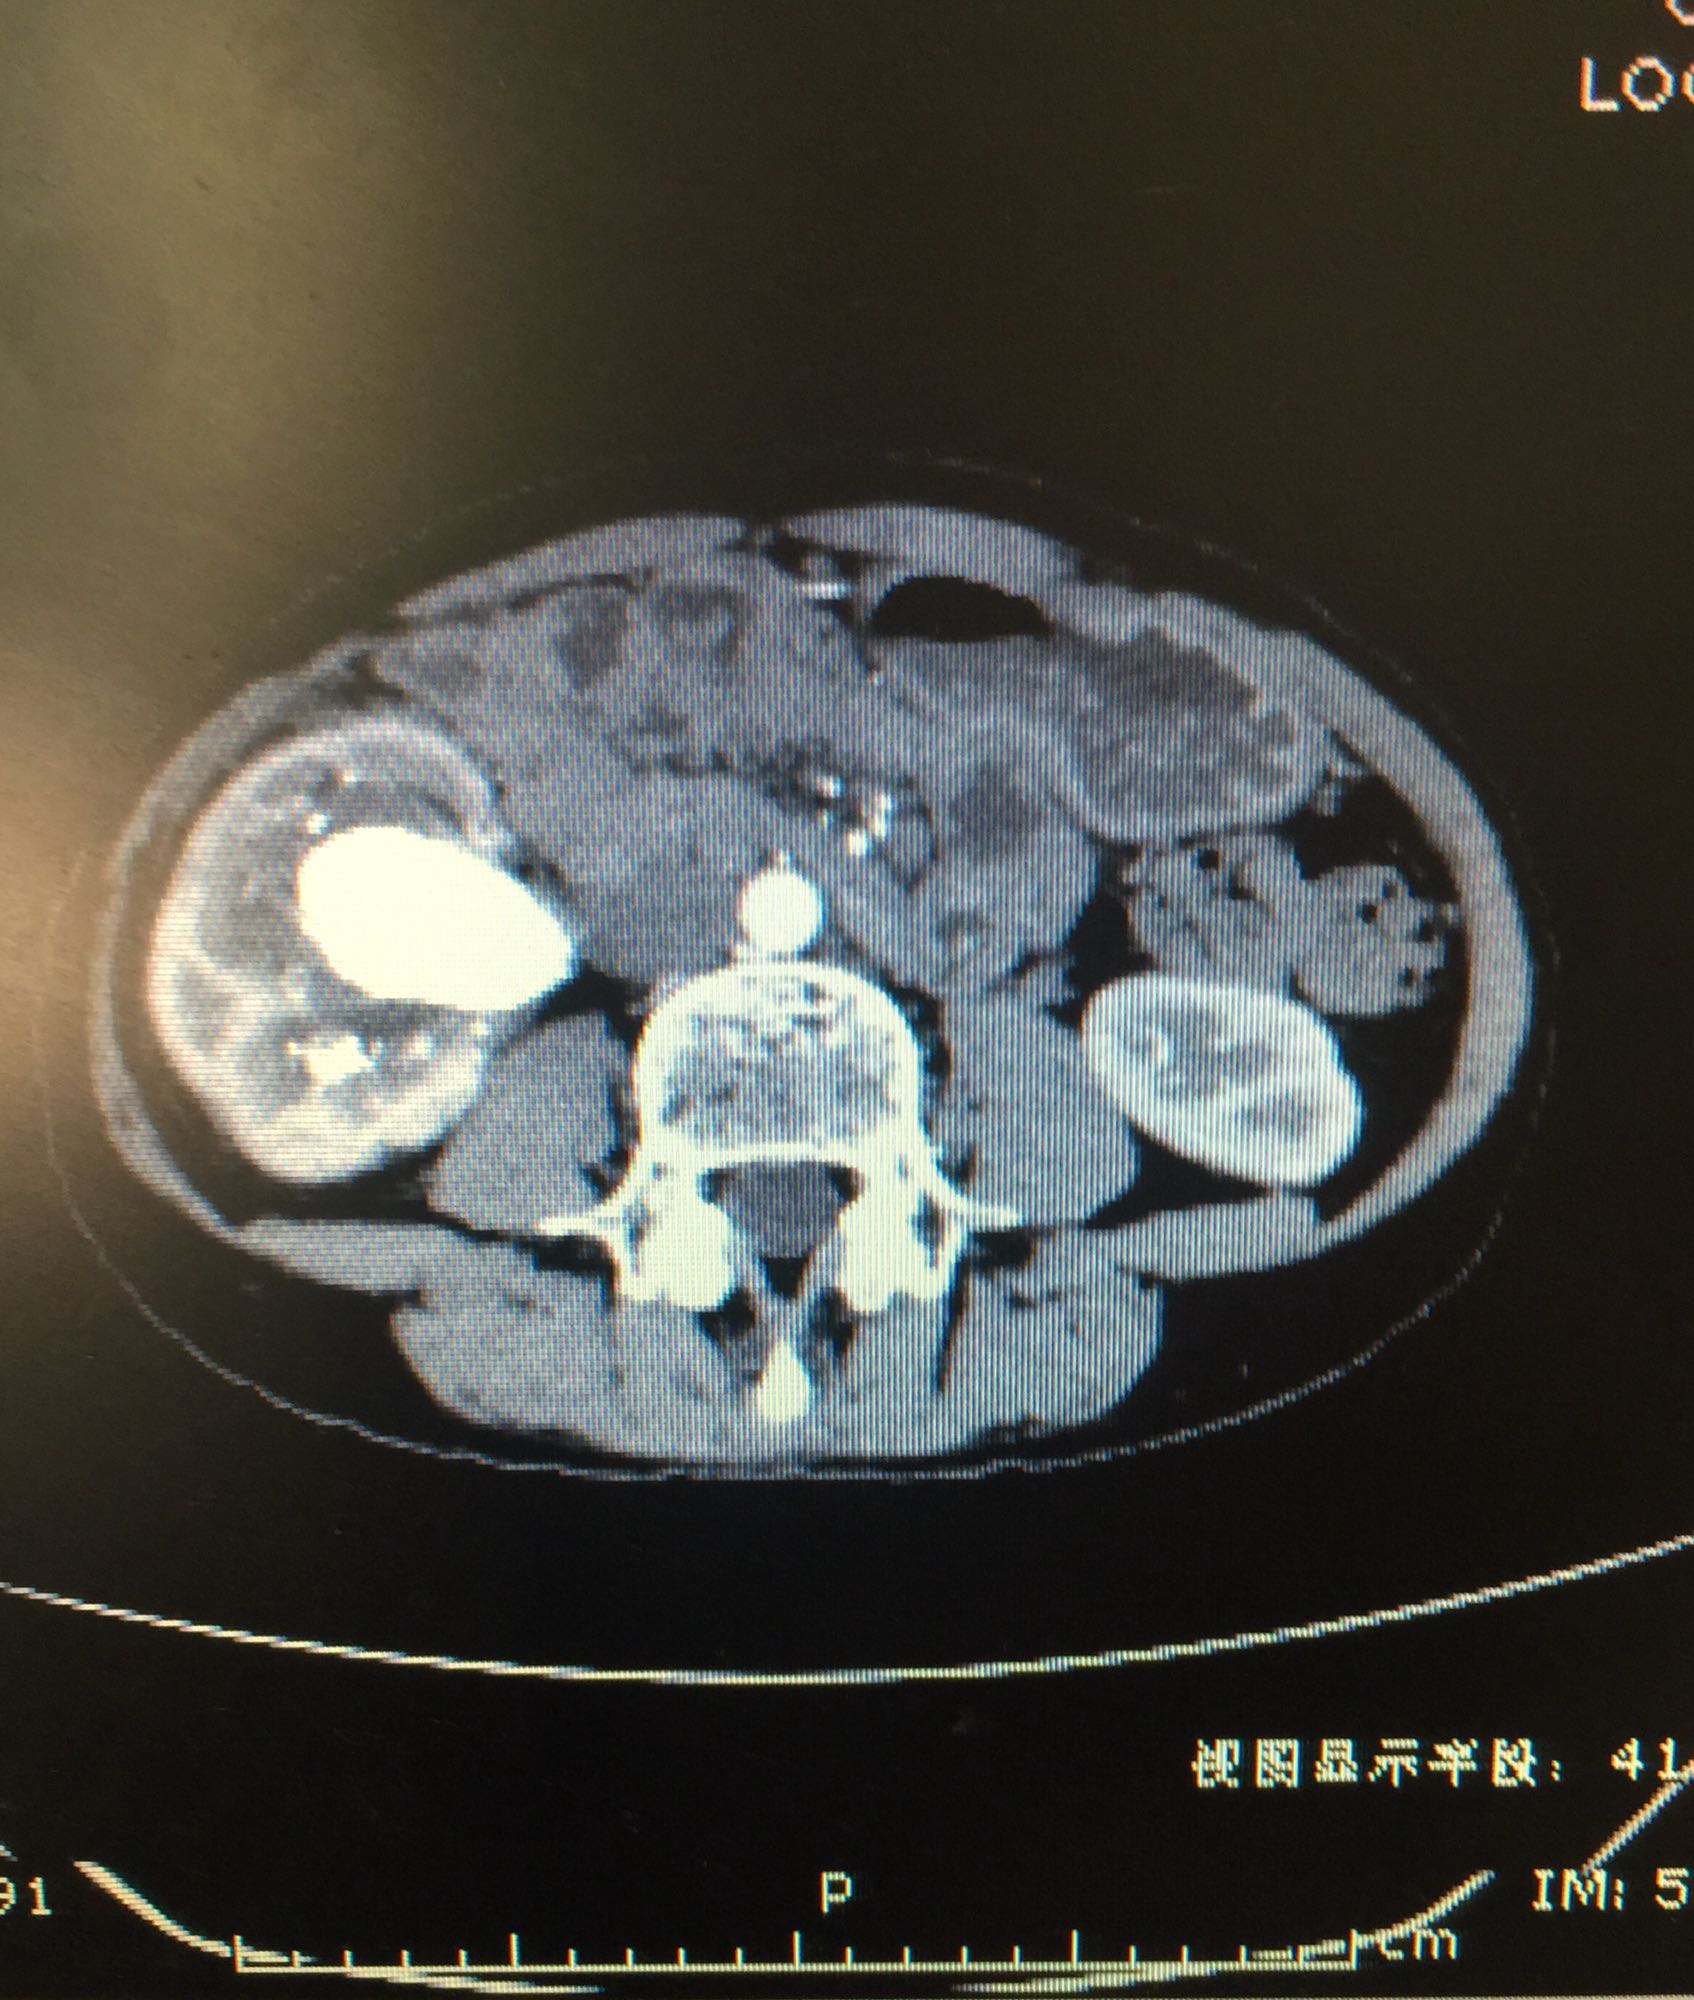

右侧肾脏巨大铸型结石一例

肾盂积水伴输尿管肾盂连接处梗阻 肾结石

右侧肾脏巨大铸型结石,右肾盂输尿管连接部狭窄? 拟完善GFR测定后决定下一步治疗方案,目前倾向于开放手术。

该患者结石大,且负荷大部分位于肾盂,肾盂几乎被填满,所以考虑是否有右侧输尿管肾盂连接部狭窄可能,结石负荷大,结合上述情况可行开放手术,一期整形 。 但若为UPJO,患者肾脏积水轻,肾脏皮质厚,肾功影响小,可能性相对小。行PCN结合超声吸附,一期清理肾盂内结石应该问题不大。 对于该患者的治疗,不知大家意见如何?